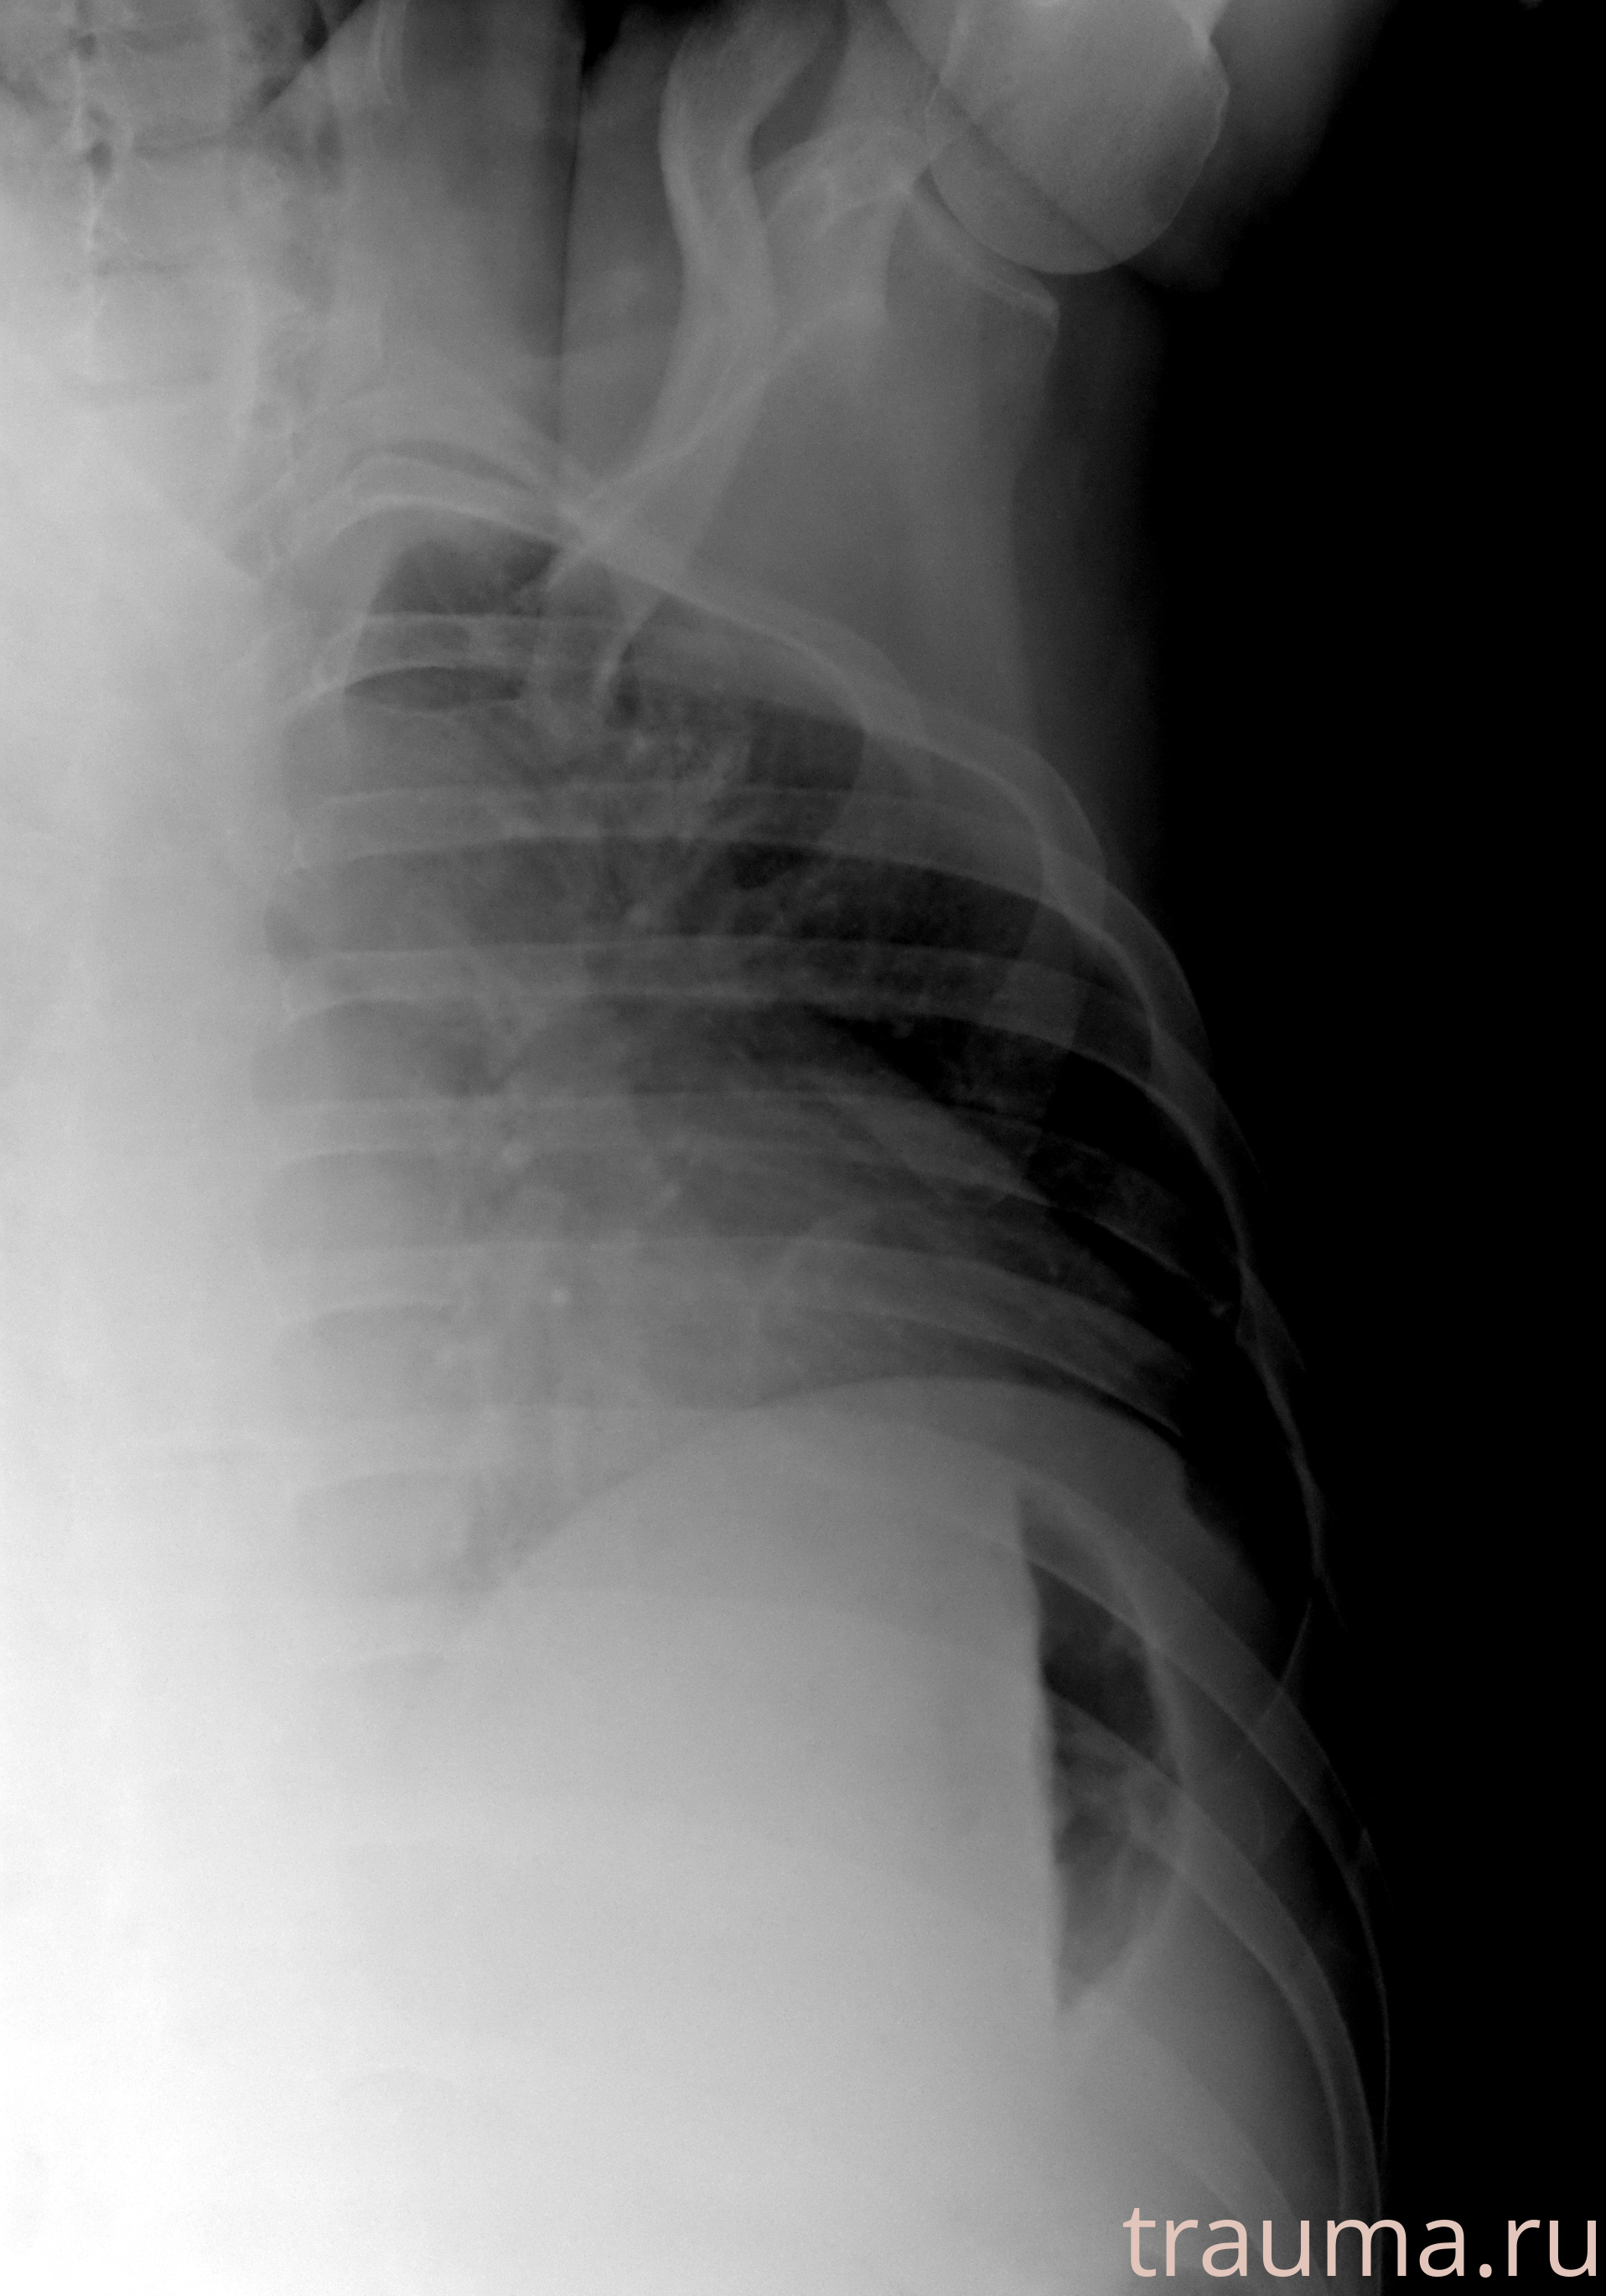

Рентгенограммы

Рентген на дому: по вашему адресу приезжает врач-рентгенолог, травматолог-ортопед с мобильным рентгеновским аппаратом, проводит диагностику травмы или заболевания, делает необходимые рентгенограммы, дает рекомендации по дальнейшему лечению. Получить качественные снимки в домашних условиях возможно благодаря уникальной методике, разработанной МосРентген Центром для института  Склифосовского

при переломе шейки бедра и пневмонии от компании МосРентген Центр - партнера Института имени Склифосовского